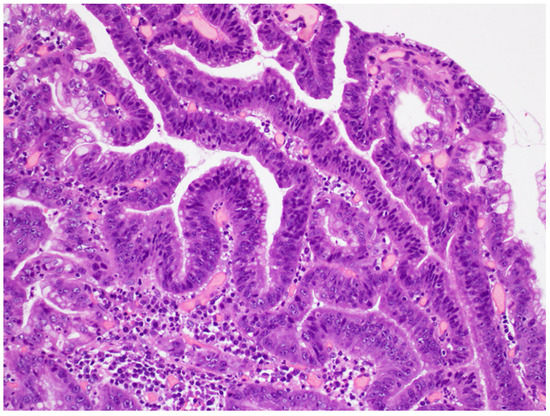

Figure 1.

Low-grade dysplasia. Glands are slightly crowed with a regular shape and size. The nuclei are cigar shaped and basally oriented.